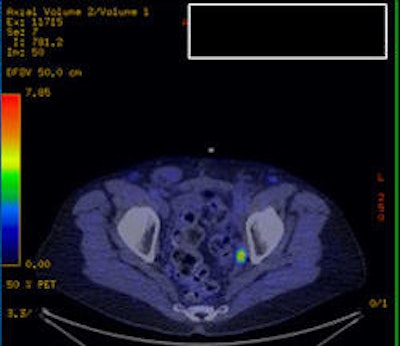

| Above is a traditional PET/CT scan of the pelvis of one individual. The image below is from a choline-PET/CT scan. The top image would appear negative to a radiologist, while the bottom scan is clearly positive for cancer, Karnes said. Images courtesy of Dr. Jeffrey Karnes. |